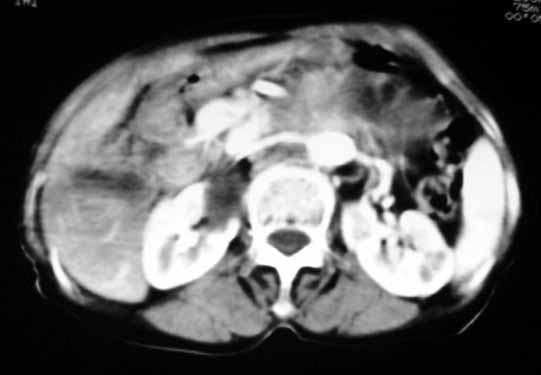

以下是引用天南地北在2007-4-30 17:42:00的发言:[br]增强扫描显示腹主动脉给包绕、推移。肿块不规则强化,[br]修正我在平扫的诊断[br]支持考虑:间叶源性肿瘤可能性大

以下是引用余辉在2007-4-30 18:01:00的发言:[br]病灶前方的条状增强影是什么?若是胰腺,位置似乎有点低,若是十二指肠,似乎又不诫该是那样强化,姑且将其看作胰腺吧,那么考虑来源于胰腺粘液囊腺瘤可能性大,其次考虑来源于肠系膜或者后腹膜的肿瘤如平滑肌肉瘤,异位嗜铬细胞瘤及淋巴瘤等。

以下是引用zyx168在2007-4-30 23:24:00的发言:[br]考虑:间叶源性肿瘤可能性大